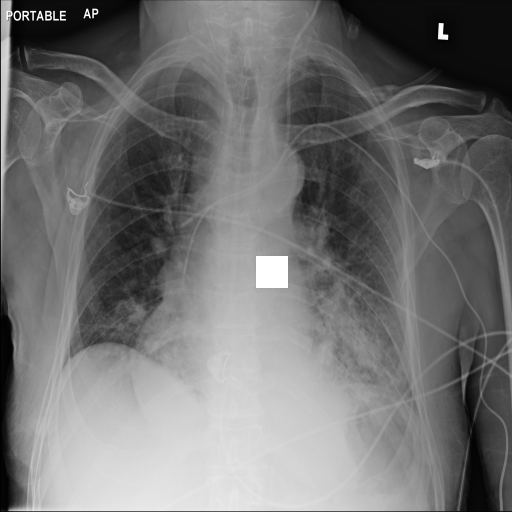

7.2 Qualitative assessment of LDP-processed CXR images

Here, we assume two possible privacy leakage scenarios. To CXR images, we intentionally add features that can lead to the re-identification of the subject appearing in a CXR image. The first feature is an artificial block marker. The second feature is a rare anatomical abnormality known as situs inversus simulated by flipping a CXR image along the vertical axis. Figs. 3(a) and 3(c) show CXR images with the artificial block marker. Fig. 5(a) shows a flipped CXR image to represent a case of situs inversus. We applied DP-GLOW to these CXR images. In Figs. 3(b) and 3(d), the image domain LDP fails to obfuscate the artificial block marker with a moderate privacy budget. In contrast, in Figs. 4(b) and 4(d), DP-GLOW successfully obfuscated the artificial block marker with the moderate privacy budget. On the other hand, the anatomical shape of the chest and the abnormal opacity (hilar regions in the case 1) are preserved. In Fig. 5(b), we observed that the right edge of the heart does not become obfuscated with the image domain LDP. In contrast, in Fig. 6(b), we observed that the right edge of the heart becomes obfuscated and the heart appears at the center of the thoracic cage with DP-GLOW. However, DP-GLOW with this privacy budget is insufficient to almost completely erase the feature of situs inversus.

Figure 3: Block obfuscation with the image domain LDP.

Figure 4: Block obfuscation with DP-GLOW.